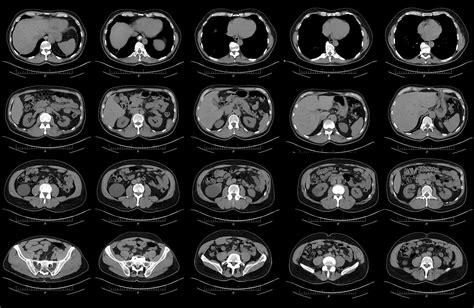

The CT Scan Procedure

The Pancreatic Adenocarcinoma CT Scan procedure is typically performed in a hospital or outpatient imaging center. The process involves the following steps:

• The patient lies on a table that slides into the CT scanner.

• The table moves slowly through the scanner, taking multiple X-ray images from different angles.

• The entire procedure usually takes about 15-30 minutes, depending on whether contrast dye is used.

• After the scan, the patient can usually resume normal activities immediately.

During the scan, it is important for the patient to remain still to ensure clear and accurate images. The technician may provide instructions to help the patient hold their breath at certain points to minimize movement.